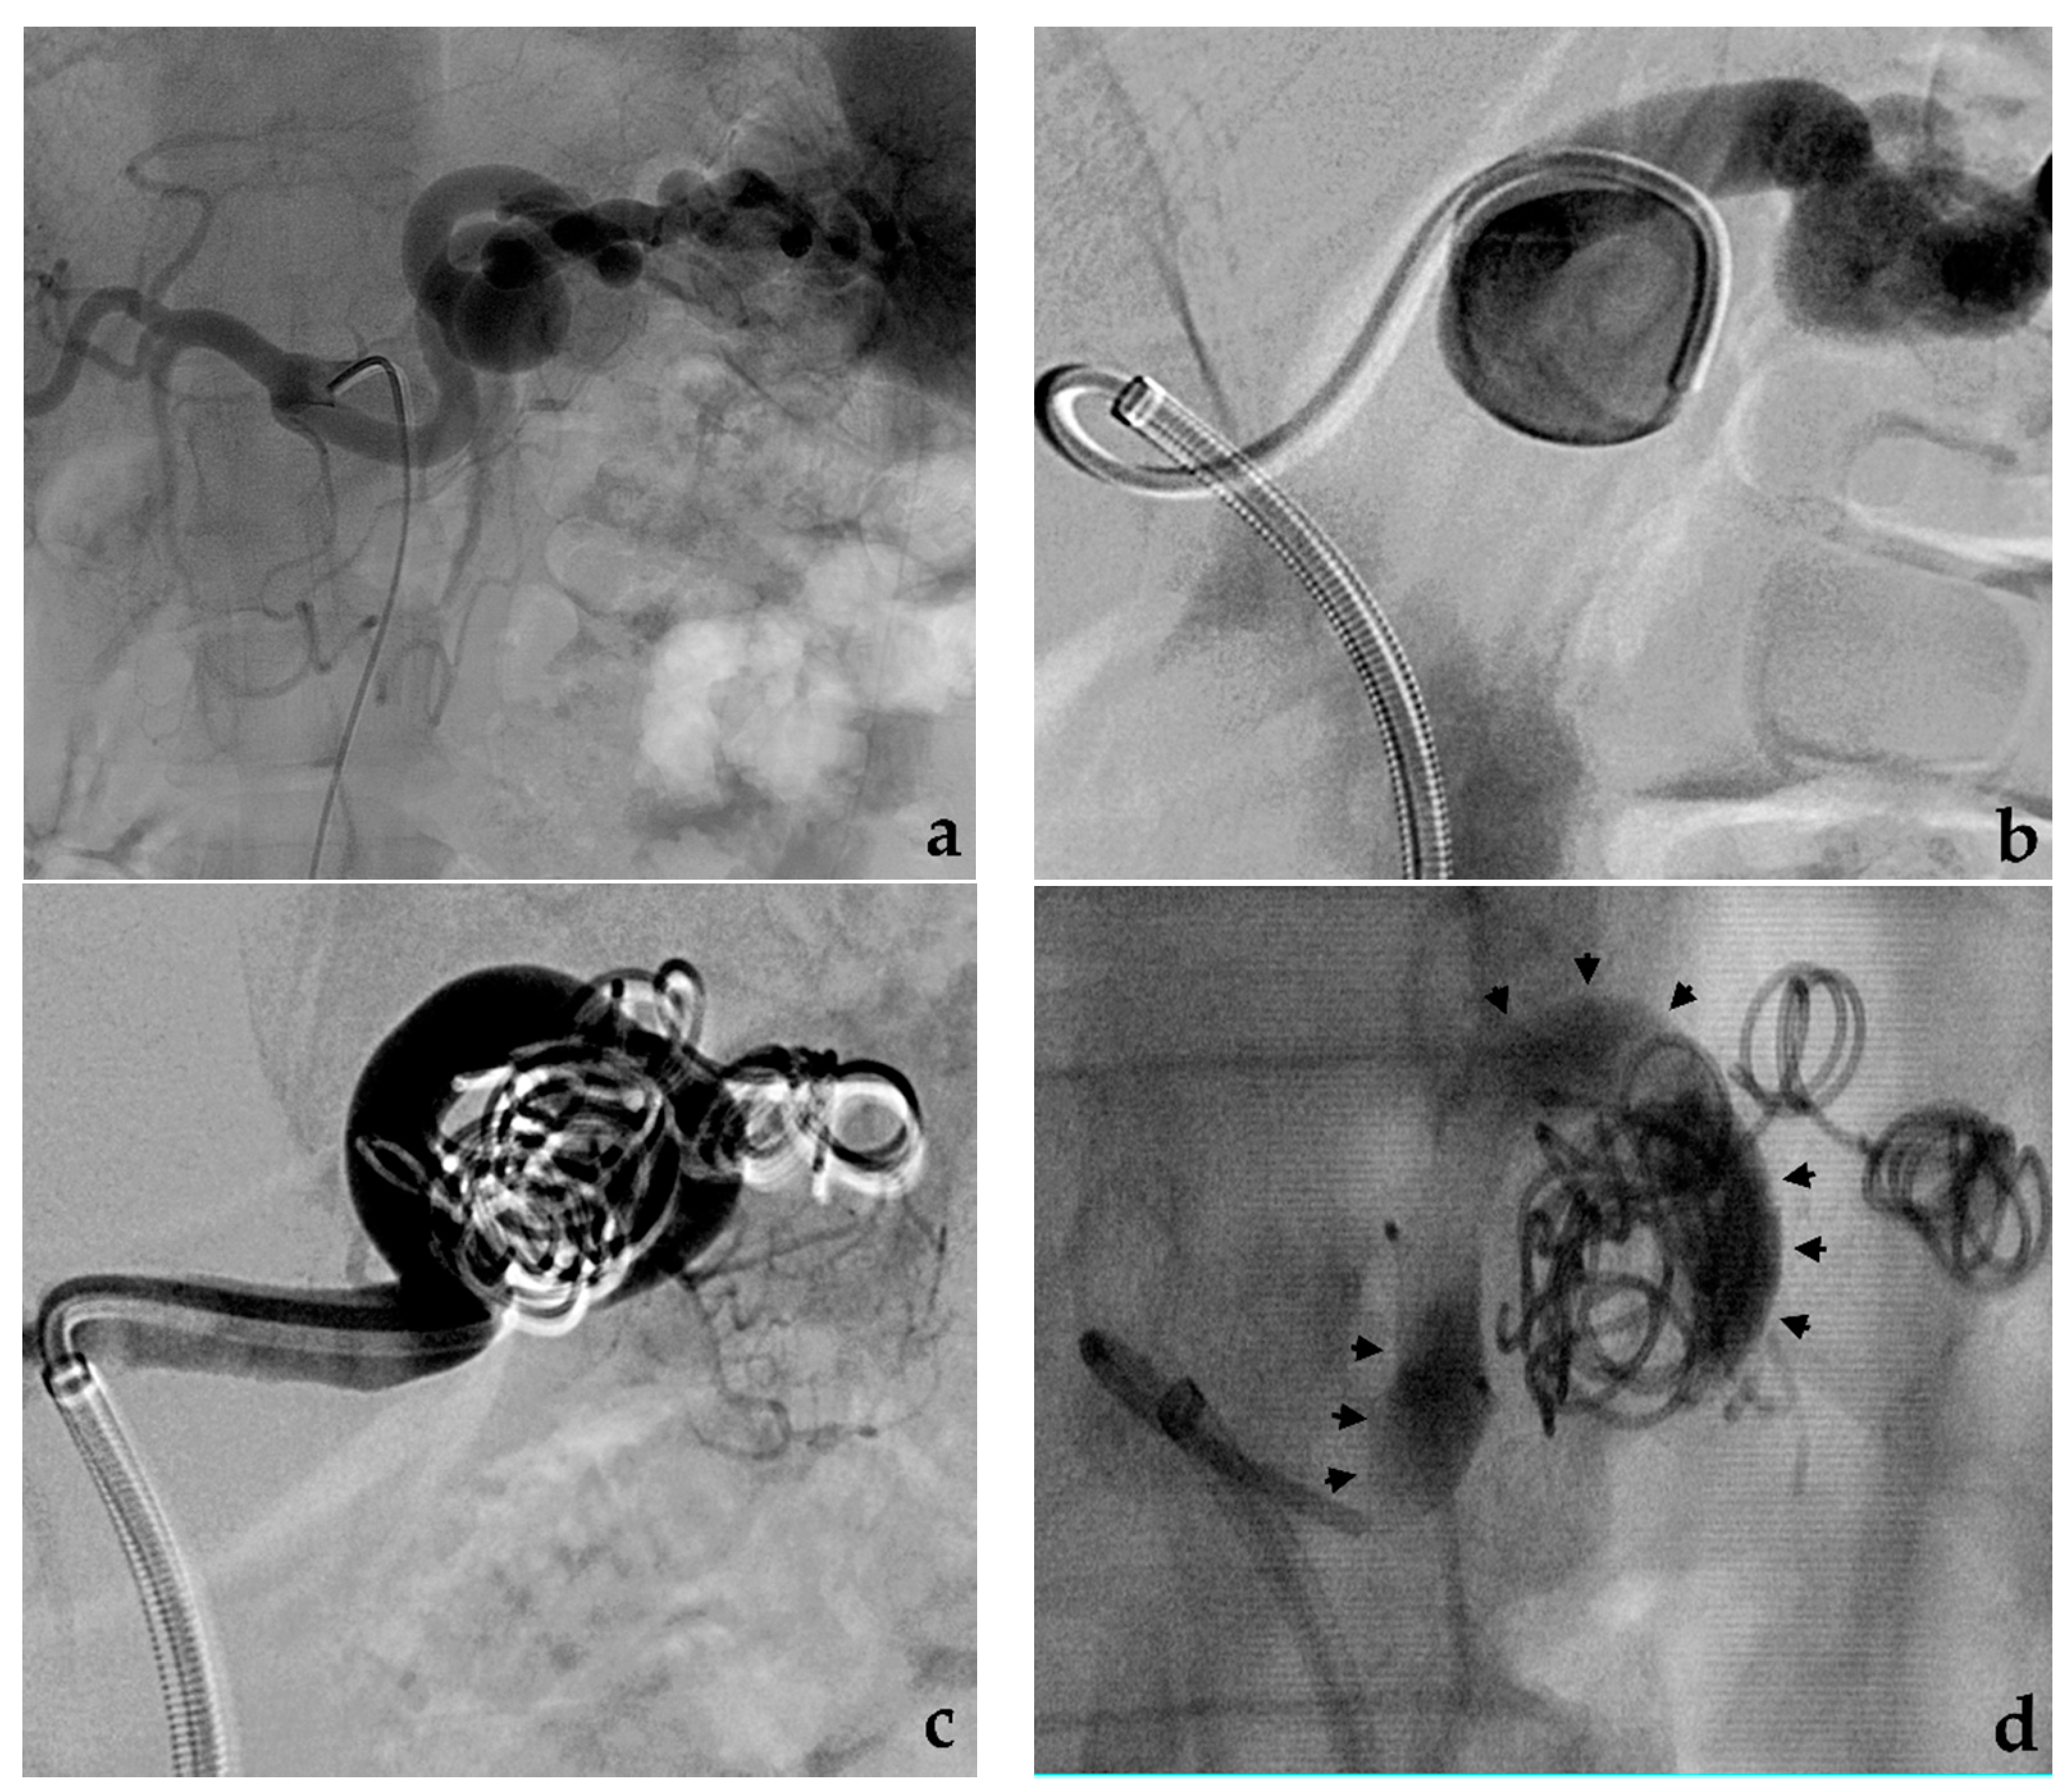

3.3. Balloon-Assisted Coil Embolization

- Onal, Y.; Samanci, C.; Cicek, E.D. Double-lumen balloons, are they only useful in neurointerventions? Preliminary outcomes of double-lumen balloon-assisted embolization of visceral artery aneurysms. Vasc. Endovasc. Surg. 2020, 54, 214–219. [Google Scholar] [CrossRef]